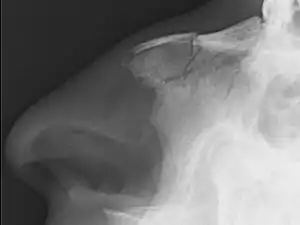

| Plain X-ray showing a nasal fracture | |

Nasal fractures are usually identified visually and through physical examination.[1] In addition, relevant questions to ask the patient include whether there is a noticeable cosmetic deformity and whether the patient has difficulty breathing through the nose after the injury. Medical imaging is generally not recommended.[1][3] A priority is to distinguish simple fractures limited to the nasal bones (Type 1) from fractures that also involve other facial bones and/or the nasal septum (Types 2 and 3). In simple Type 1 fractures X-Rays supply surprisingly little information beyond clinical examination. However, diagnosis may be confirmed with X-rays or CT scans, and these are required if other facial injuries are suspected.[3]